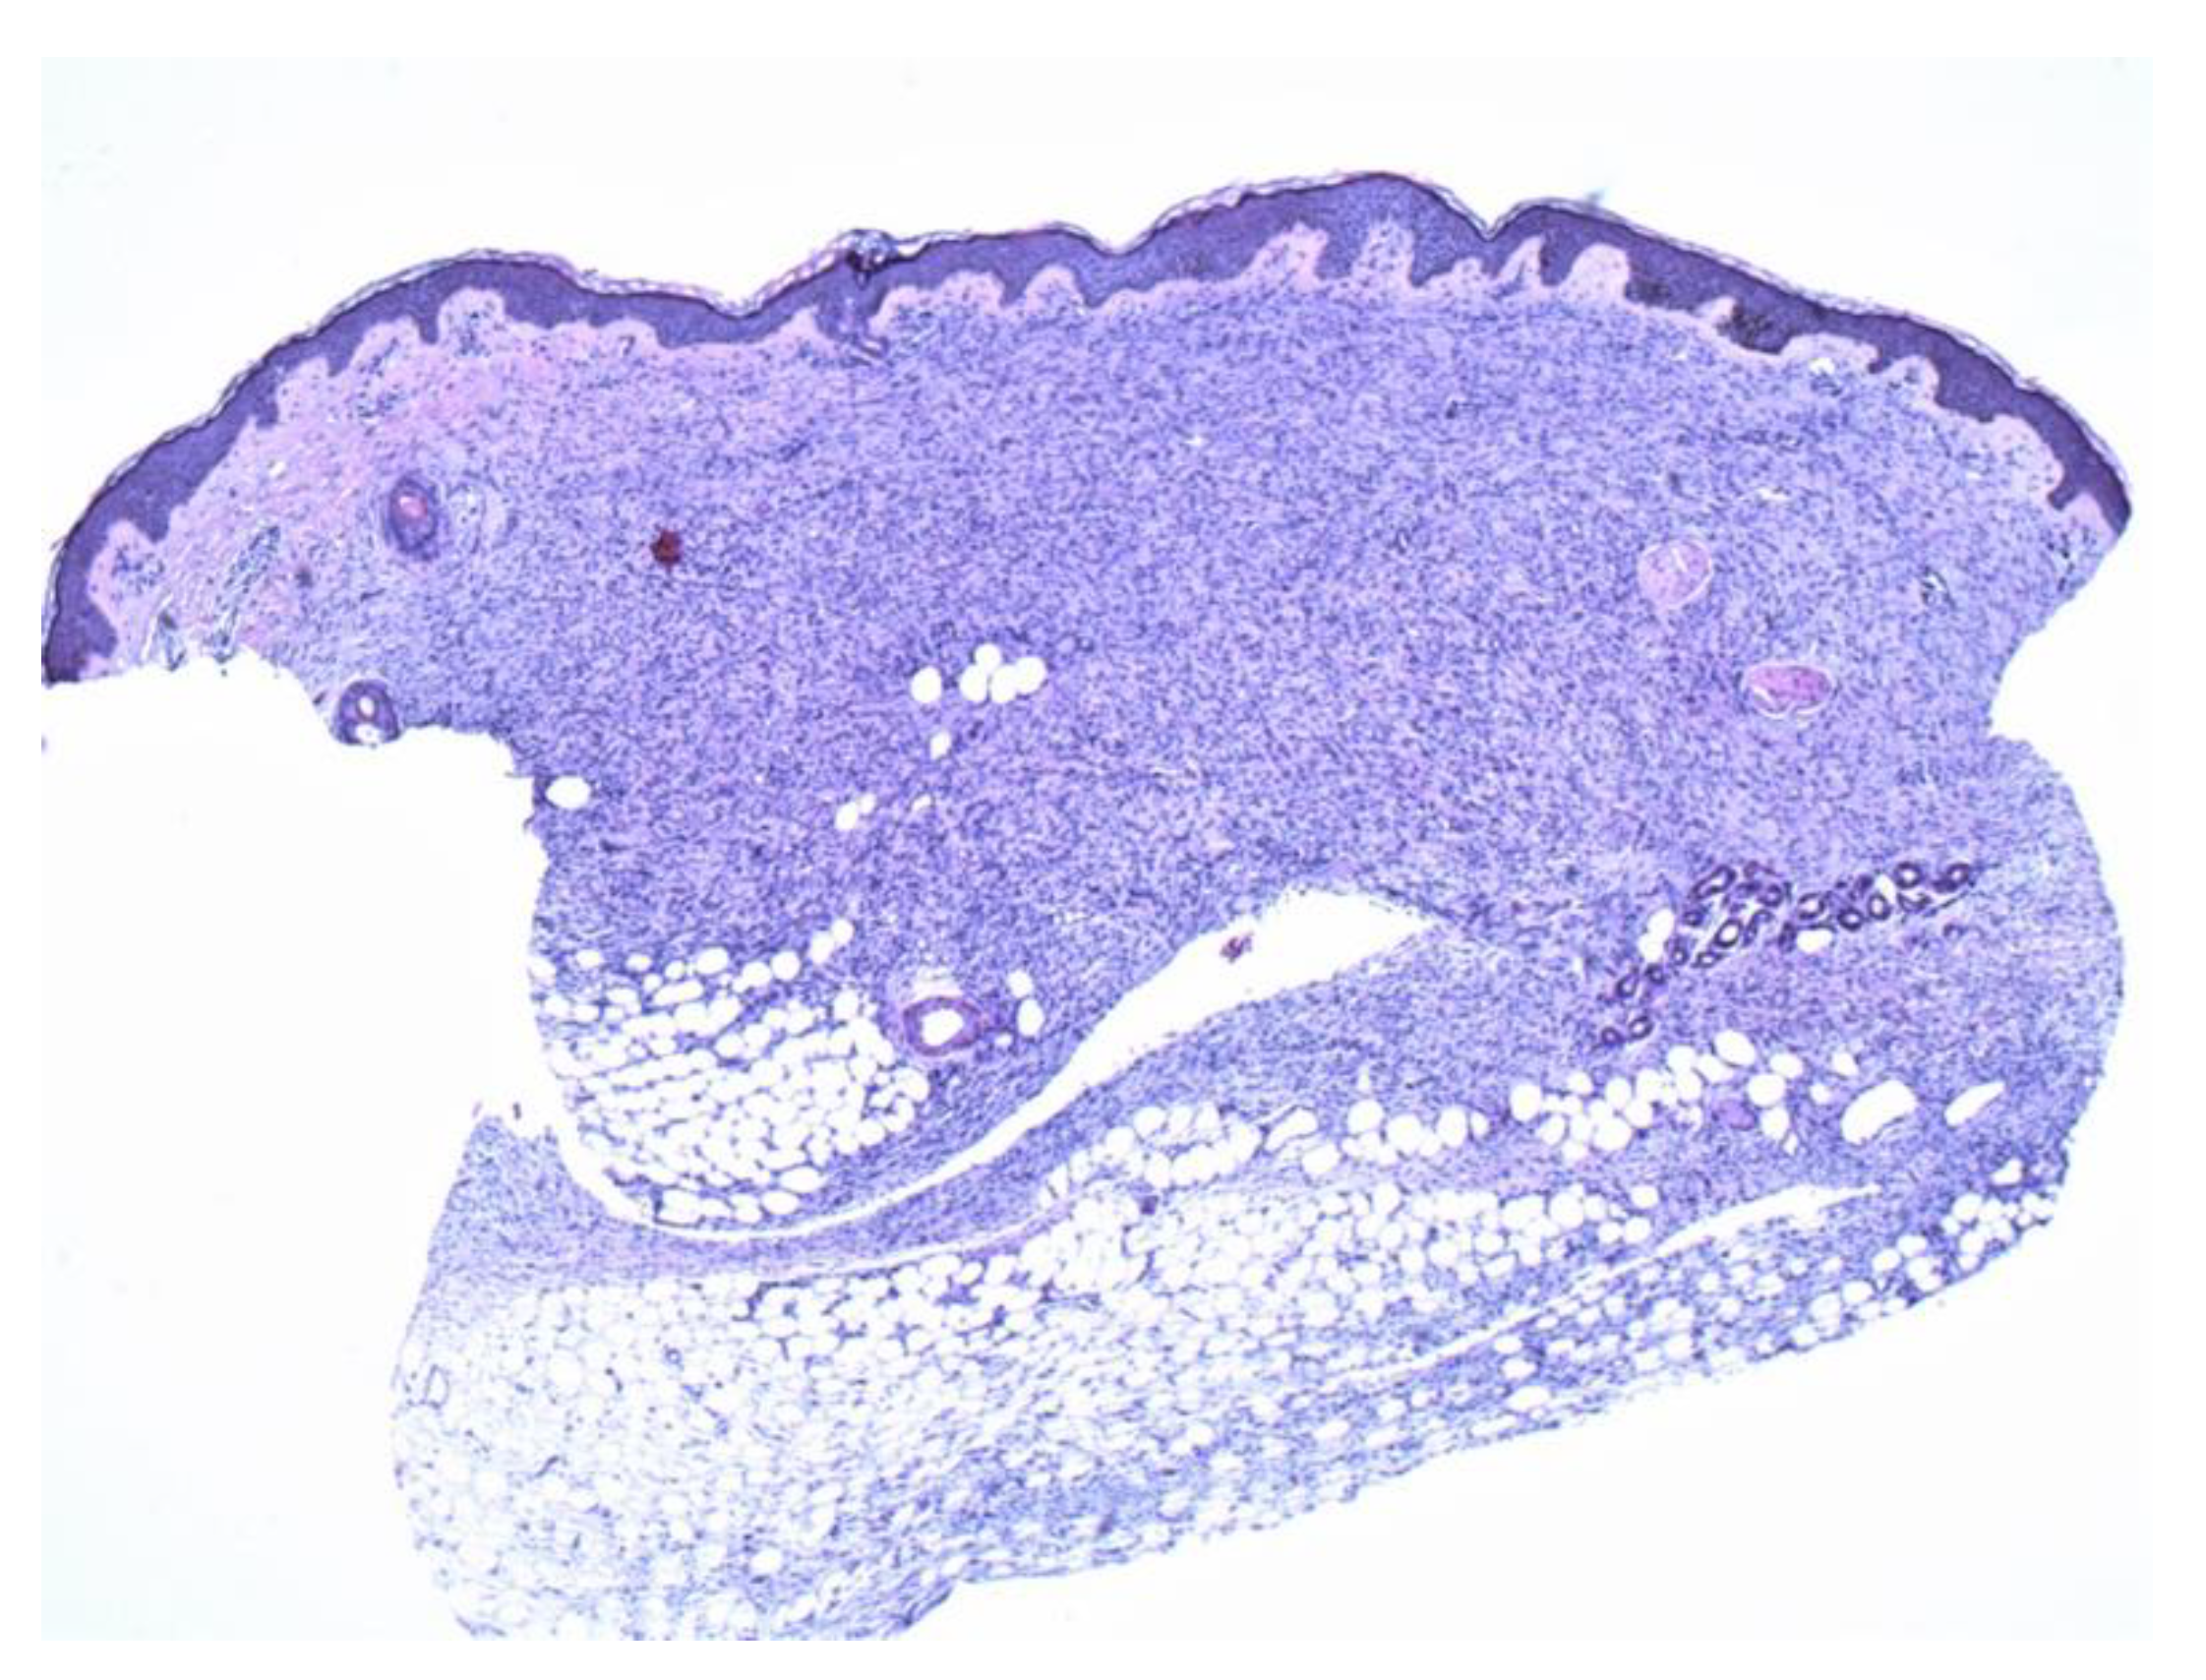

Figure 5.

The second biopsy shows diffuse and even involvement of the dermis (4×).